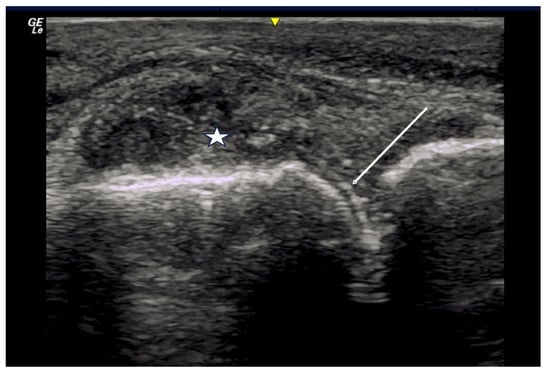

2.1.3. Acro-Osteolysis

2.6. Calcium Deposition

3. Materials and Equipment